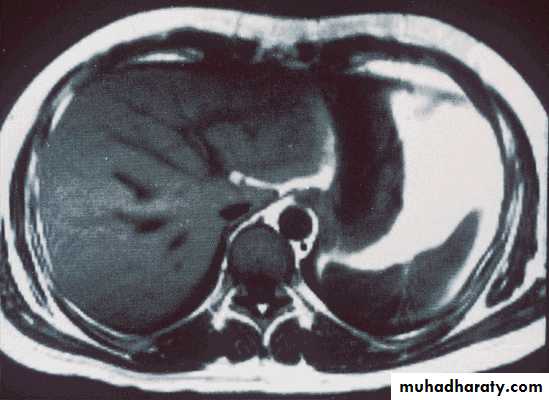

Normal liver MRI